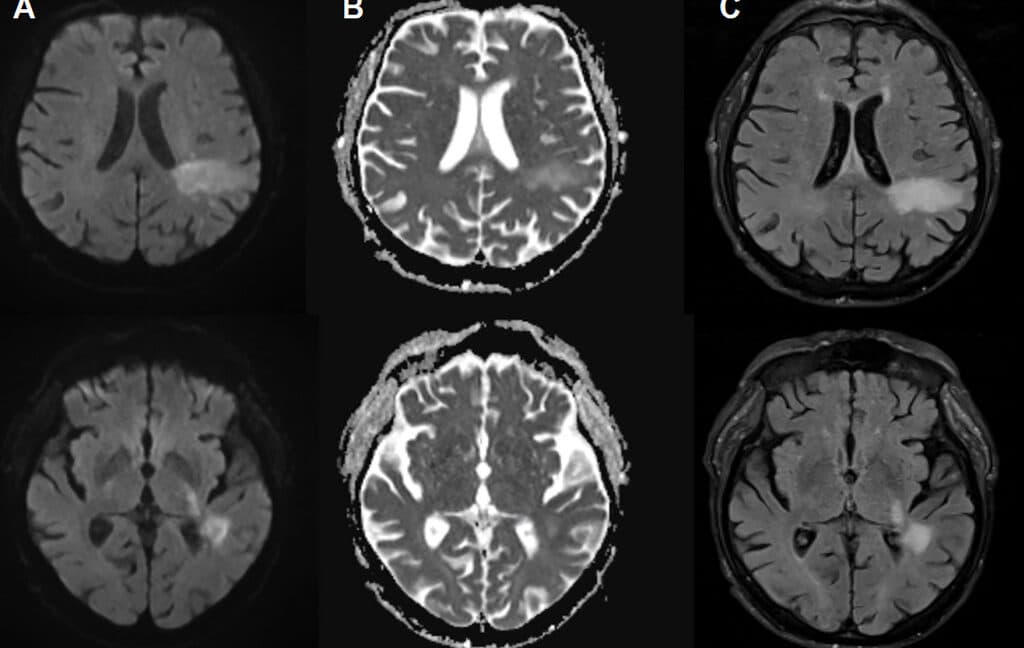

- Activation of JC virus could destroy brain tissue if triggered.

“There’s a virus you may have never heard of before that is estimated to infect up to 90 percent of people and lurks quietly in your cells for life—but if it becomes activated, it will destroy your brain”